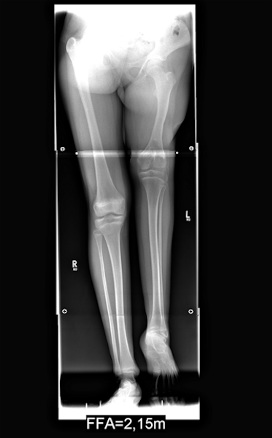

Diagnose: Beinverkürzung links durch einen 21 cm zu kurzen Oberschenkelknochen bei einer Gesamtkörpergröße von 172 cm

Therapie: Verlängerung des linken Oberschenkelknochens mittels Distraktionsverfahren nach Ilisarow um 18 cm Anpassende Verkürzung des rechten Oberschenkelknochens um 3cm